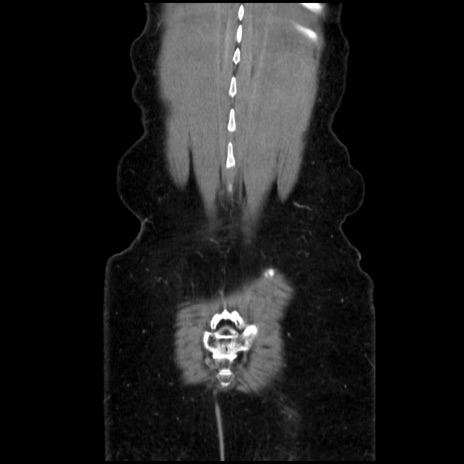

横断像

矢状断像

【症例】40歳代 女性

【主訴】上腹部痛、嘔気・嘔吐

【現病歴】約9時間前頃から急に上腹部痛、嘔気、嘔吐が出現。改善しないため救急要請。

【既往歴】子宮頚癌(広汎子宮全摘術、放射線療法)、腸閉塞